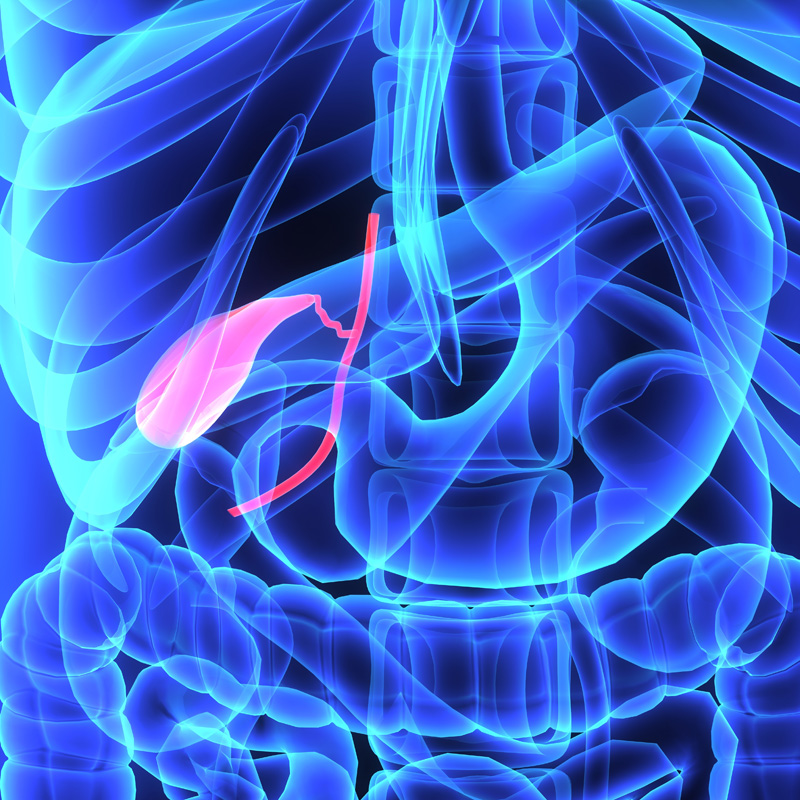

Le cancer de la vésicule biliaire est une maladie insidieuse. Son développement initial se fait souvent de manière silencieuse. Les symptômes, lorsqu'ils se manifestent, sont parfois vagues et peuvent être attribués à d'autres affections moins graves. Une vigilance accrue est donc cruciale.

La vésicule biliaire joue un rôle essentiel dans la digestion des graisses. Un dysfonctionnement, causé par une tumeur, perturbe ce processus. Plusieurs symptômes digestifs peuvent alors apparaître.

La bilirubine est un pigment jaune produit lors de la dégradation des globules rouges. Normalement, la vésicule biliaire et le foie contribuent à son élimination. Une obstruction des voies biliaires, causée par une tumeur, empêche cette élimination.

Médicalement en rendu 3d illustration de l'exacte du cancer de la